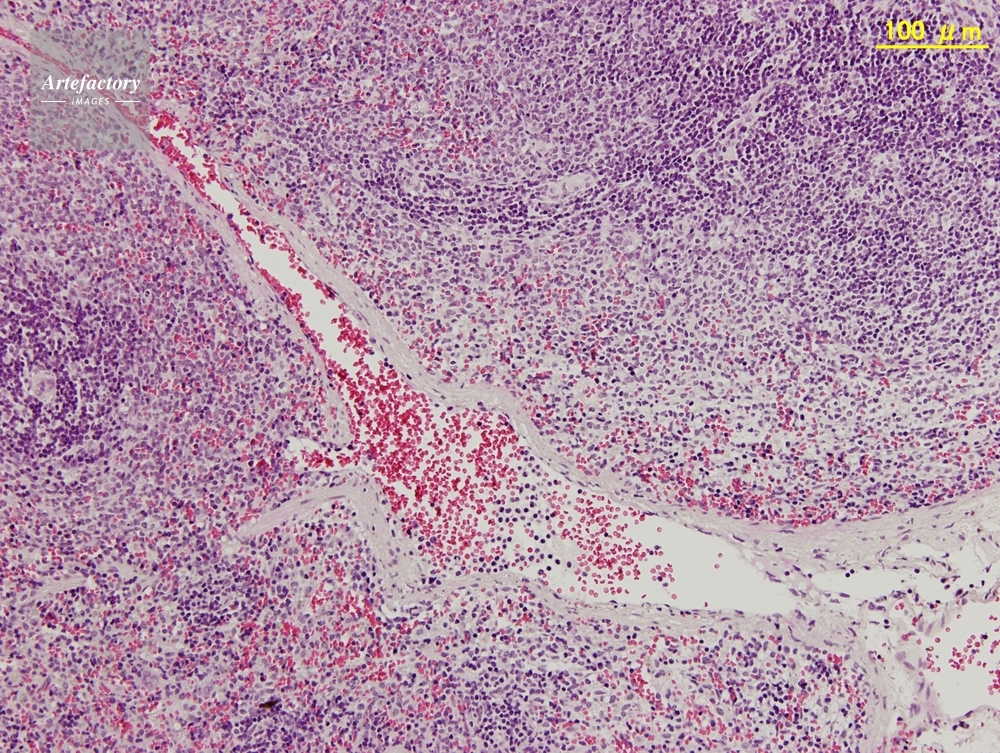

| 作品タイトル | マウス,脾臓 | モデルリリース | なし | |

| 作家 | OLYMPUS CORPORATION Technolab | プロパティリリース | なし | |